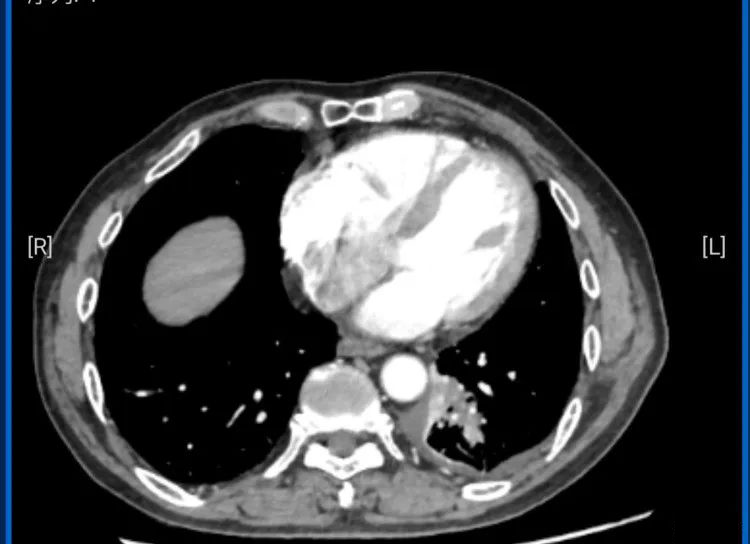

胸部增强CT显示

其左肺下叶支气管闭塞伴远端肺不张,

建议进一步支气管镜检查。